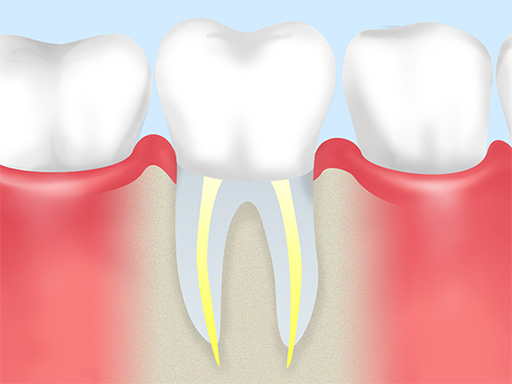

- 05

経過観察 -

術後のレントゲン検査と診察で、治療の成果を確認します。

- 06

被せ物の治療 -

根管治療を終えた歯を守るために、適合性の高い被せ物を装着します。